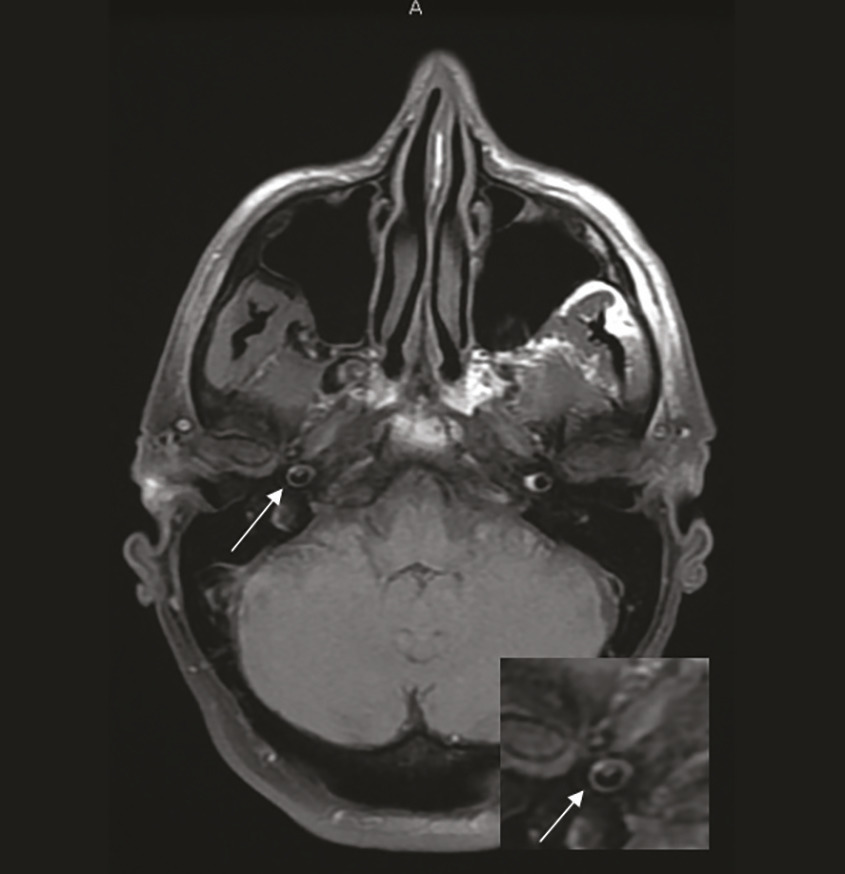

Cet homme de 59 ans consultait pour une gêne de l’œil gauche apparue la veille. Il était traité pour une hypertension artérielle, une dyslipidémie et un accident ischémique transitoire (AIT). À l’examen, on notait un ptôsis, un myosis réactif et une enophtalmie de l’œil gauche (fig. 1) , faisant évoquer un syndrome de Claude-Bernard-Horner. L’IRM cérébrale montrait un aspect irrégulier des carotides internes avec un aspect de pseudo-anévrisme et d’hématome de paroi de la carotide interne droite (fig. 2) (pas d’infarctus cérébral). L’angio-IRM (ARM) cervico-encéphalique confirmait la dissection bicarotidienne avec pseudo-anévrisme bilatéral. Le patient était traité, par héparine non fractionnée (HNF) curative, avec un relai par antivitamine K (AVK). Il était réadmis pour des céphalées irradiant dans l’œil gauche et le cou, des nausées, une photo-phonophobie, et une faiblesse de la jambe droite. L’ARM montrait une dissection bicarotidienne. Le patient avait secondairement un déficit hémicorporel droit suspect d’un AIT carotidien gauche compliquant la dissection carotidienne. L’anticoagulation curative par AVK était maintenue.